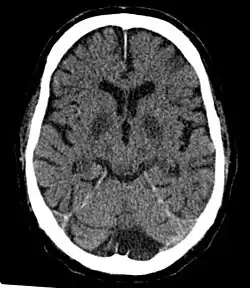

Cerebral hypoxia is a form of hypoxia (reduced supply of oxygen), specifically involving the brain; when the brain is completely deprived of oxygen, it is called cerebral anoxia. There are four categories of cerebral hypoxia; they are, in order of increasing severity: diffuse cerebral hypoxia (DCH), focal cerebral ischemia, cerebral infarction, and global cerebral ischemia. Prolonged hypoxia induces neuronal cell death via apoptosis, resulting in a hypoxic brain injury.[1][2]

Cases of total oxygen deprivation are termed "anoxia", which can be hypoxic in origin (reduced oxygen availability) or ischemic in origin (oxygen deprivation due to a disruption in blood flow). Brain injury as a result of oxygen deprivation either due to hypoxic or anoxic mechanisms is generally termed hypoxic/anoxic injury (HAI). Hypoxic ischemic encephalopathy (HIE) is a condition that occurs when the entire brain is deprived of an adequate oxygen supply, but the deprivation is not total. While HIE is associated in most cases with oxygen deprivation in the neonate due to birth asphyxia, it can occur in all age groups and is often a complication of cardiac arrest.[3][4][5]